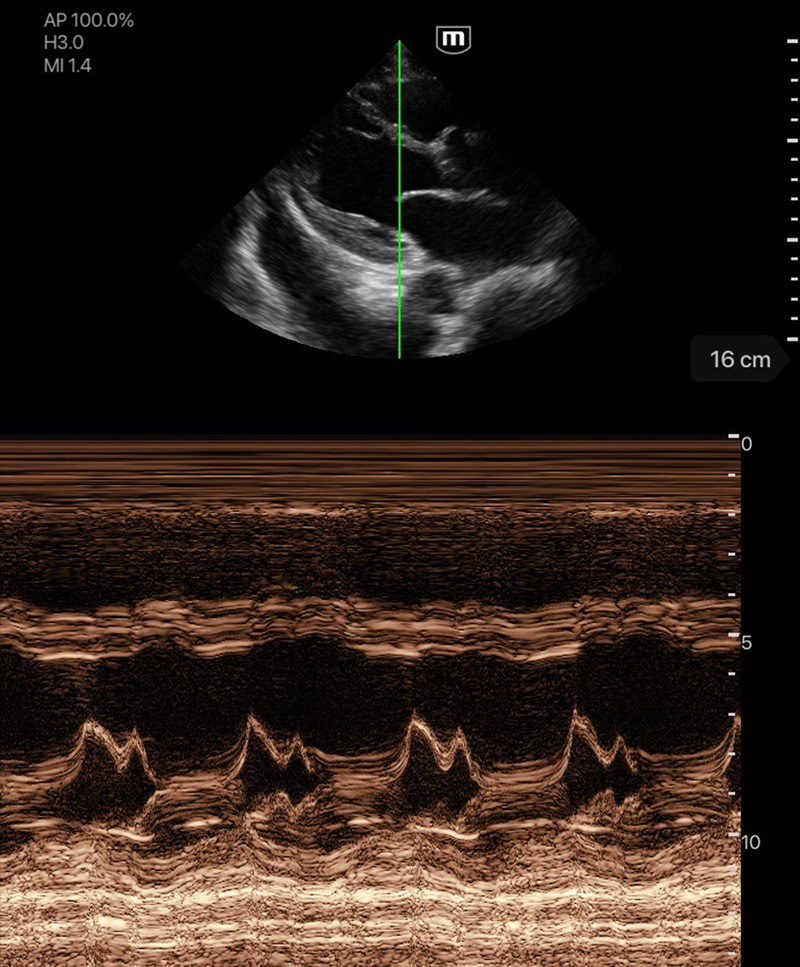

Immagini cliniche

Rigurgito mitrale e tricuspidale

Effusione pericardica

Ascite

Cardiomiopatia dilatativa

Doppler della velocitأ tissutale

Linea B polmonare

Immagini cliniche

Rigurgito mitrale e tricuspidale

Effusione pericardica

Ascite

Cardiomiopatia dilatativa

Doppler della velocitأ tissutale

Linea B polmonare